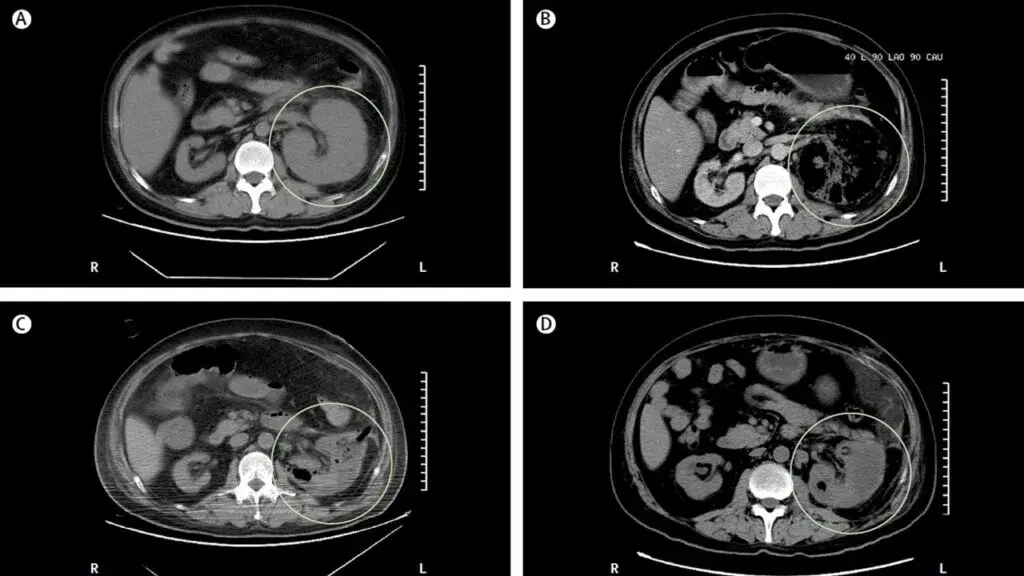

Um homem de 39 anos foi internado no hospital com história dia com dor no flanco esquerdo e tontura há um dia. Paciente tinha antecedentes de diabetes mal controlado e nefrolitíase obstrutiva à esquerda. Após avaliação inicial a TC do abdome mostrou aumento do tamanho do rim esquerdo devido gás no parênquima renal, espaço perirrenal e veia renal. Foi instituído tratamento com antibióticos e realizado de cirurgia aberta (elevado risco de embolização). O paciente evoluiu com melhora clínica e radiológica, TC de controle após 04 dias já mostrou redução do gás e do volume renal. Qual é o diagnóstico?

Caso típico de **pielonefrite enfisematosa** publicado no The Lancet ([link](https://www.thelancet.com/journals/lancet/article/PIIS0140-6736(19)30771-8/fulltext)). Os casos geralmente são decorrentes de infecção por _Escherichia coli_ em pacientes com diabetes descompensado e obstrução do trato urinário. A glicose é um substrato para proliferação de bactérias fermentadoras (_Enterobacteriaceae_), que produzem gás carbônico e hidrogênio. **Fica a dica do elevado risco de embolização**. Quando presente obstrução, a desobstrução da via urinária é mandatória. Nos casos com gás no parênquima ou espaço perirrenal, é sugerido fortemente drenagem percutânea, caso o gás fique limitado ao espaço coletor (pielite isolada) o manejo com antibióticos é suficiente.